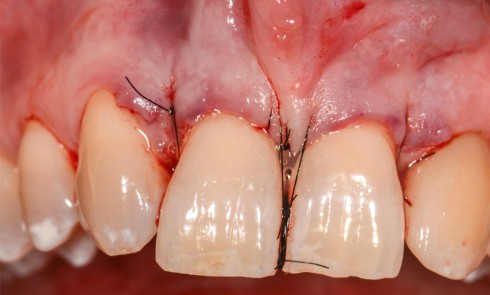

Parodontologie

Article réservé à nos abonnés Synergie ortho-parodontale dans le traitement d’une lésion infra-osseuse associée à une migration dentaire secondaire

La parodontite de stade IV entraîne fréquemment le déplacement des dents antérieures maxillaires et elle est souvent associée à des...